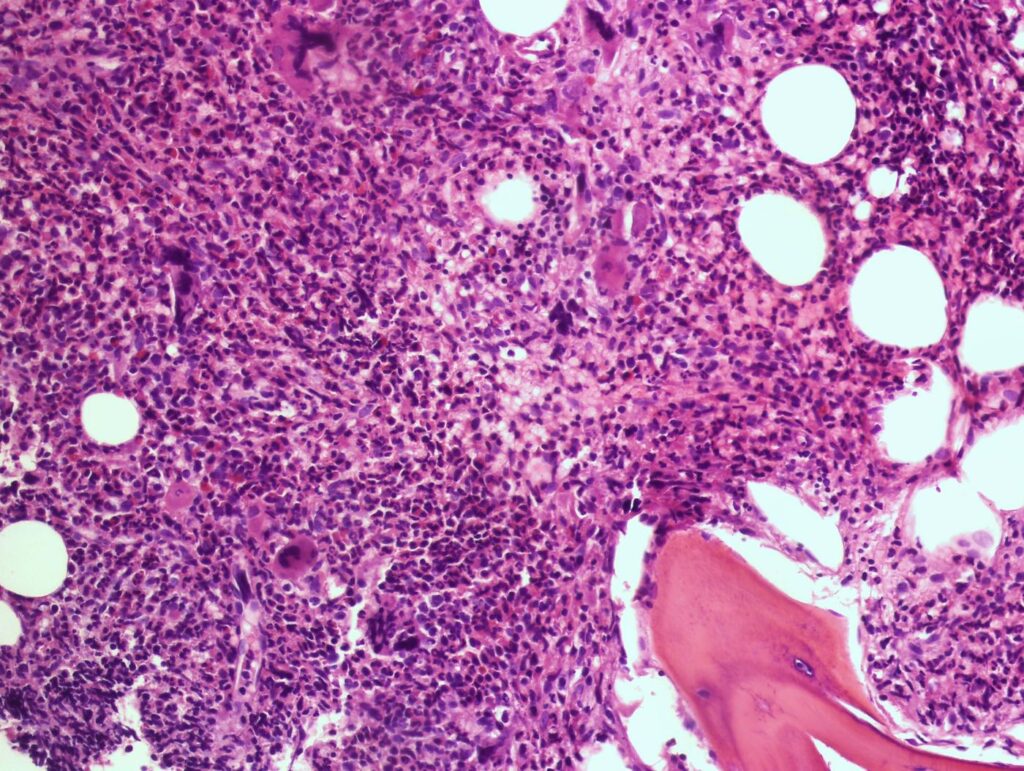

Tipos histológicos de neoplasia trofoblástica gestacional

El diagnóstico de neoplasia trofoblástica gestacional por lo general se realiza a través de niveles de gonadotropina coriónica humana en suero persistentemente elevados aún sin confirmación por un estudio de…